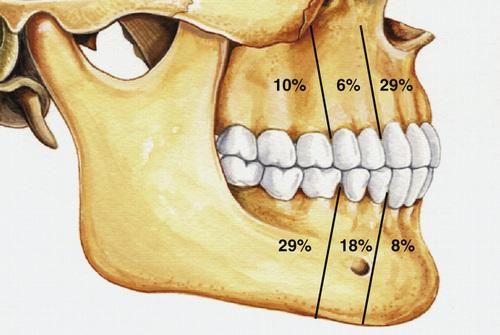

What are the three different clinicoradiographic presentations of ameloblastoma?

- conventional solid or multicystic (80%)

- unicystic (18%)

- peripheral or extraosseous (2%)